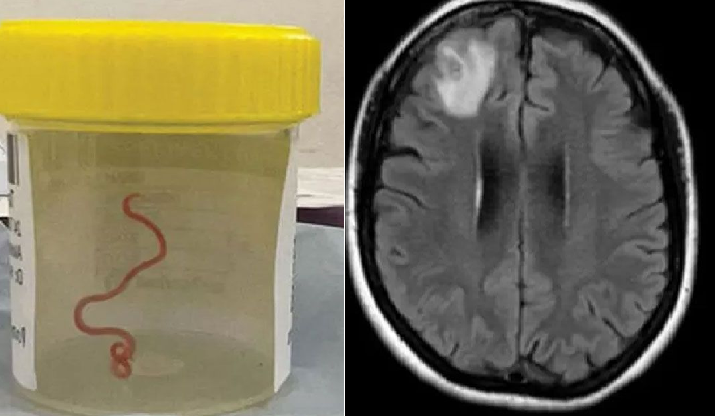

আমাদের কাগজ ডেস্ক : এবার মানব মস্তিষ্কে পাওয়া গেল জীবন্ত গোলকৃমি। ঘটনাটি ঘটেছে, অস্ট্রেলিয়ায় এক নারীর সাথে। এ সময় আট সেন্টিমিটার লম্বা একটি গোলকৃমি জীবিত অবিস্থায় পাওয়া গেছে ওই নারীর মস্তিষ্কে।

আল জাজিরার মঙ্গলবারের প্রতিবেদনে বলা হয়, অস্ট্রেলিয়ান ন্যাশনাল ইউনিভার্সিটি (এএনইউ) ও ক্যানবেরা হাসপাতালের নিউরোসার্জন ডা. হরি প্রিয়া বান্দি অস্ত্রোপচার করে নারীর মস্তিষ্ক থেকে জীবন্ত গোলকৃমি বের করেন।

৬৪ বছর বয়সী ওই নারী ২০২১ সালে স্থানীয় একটি হাসপাতালে ভর্তি হন ডায়রিয়া ও পেটে ব্যথার উপসর্গ নিয়ে। সেখানকার চিকিৎসকেরা তার রোগ নির্ণয় করতে না পারলে বছর খানেক পর ক্যানবেরা হাসপাতাল ভর্তি হন তিনি।পরে তার মস্তিষ্কের এমআরআই করার পর অস্বাভাবিক কিছু দেখা গেলে সার্জারির প্রয়োজন হয়।